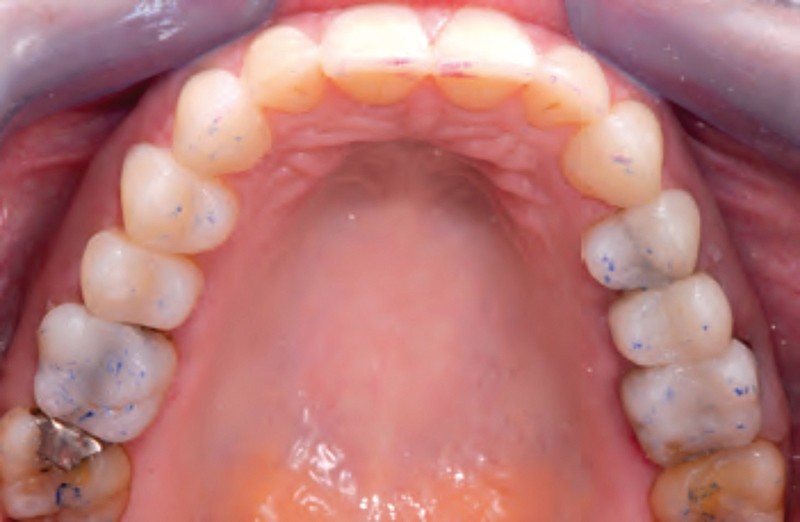

Jean-Pierre Attal : Tout à fait. Mais il faudra donner au prothésiste un maximum d’indications pour qu’il puisse réaliser sa cire de diagnostic. Vous découvrirez que la première étape de la réalisation de ces « full mock-up » est la réalisation d’un projet esthétique virtuel [8] à partir de cadrages photographiques précis aux trois échelles (visage, sourire, dento-gingivale). Gil Tirlet nous expliquera tout cela en détail avec des vidéos que j’ai déjà visionnées et qui sont très impressionnantes (fig. 1 à 4) !

Jean-Pierre Attal : Exactement, car il est possible d’appliquer le protocole de la technique « 3 steps » aux patients présentant des pertes de substance d’origine attritive (bruxisme) (fig. 5).